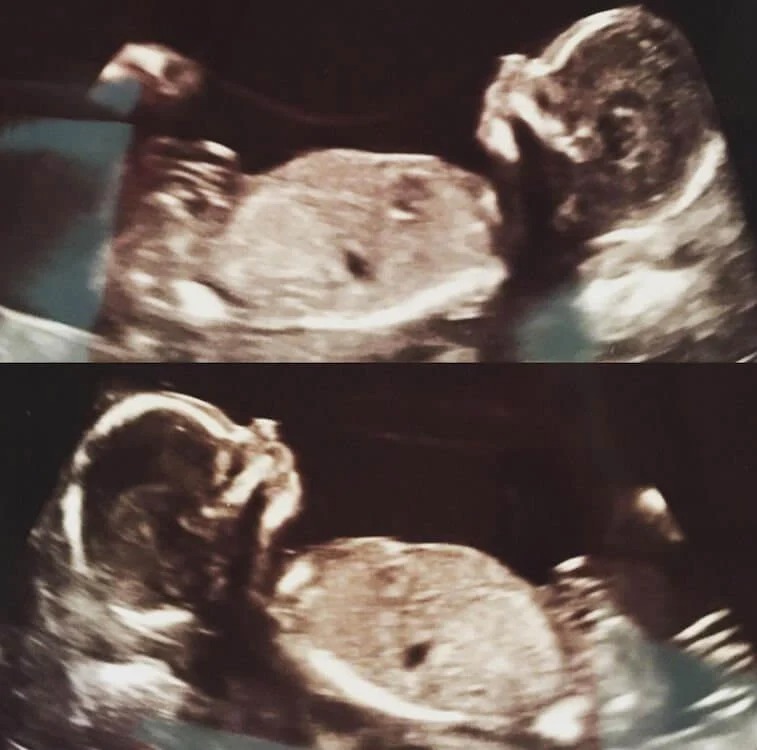

För när de skulle på sin första ultraljudsundersökning fick de ny information, de väntade tvillingar!

De började titta på familjens historia, för att se om det fanns några fall av tvillingar. De upptäckte snart att det fanns olika icke-identiska tvillingar i båda deras familjer, men ingen av dem hade någonsin varit identisk.

I december 2016 kunde de välkomna identiska tvillingpojkar vid namn Jack och Wolfe till världen, och de var helt perfekta.